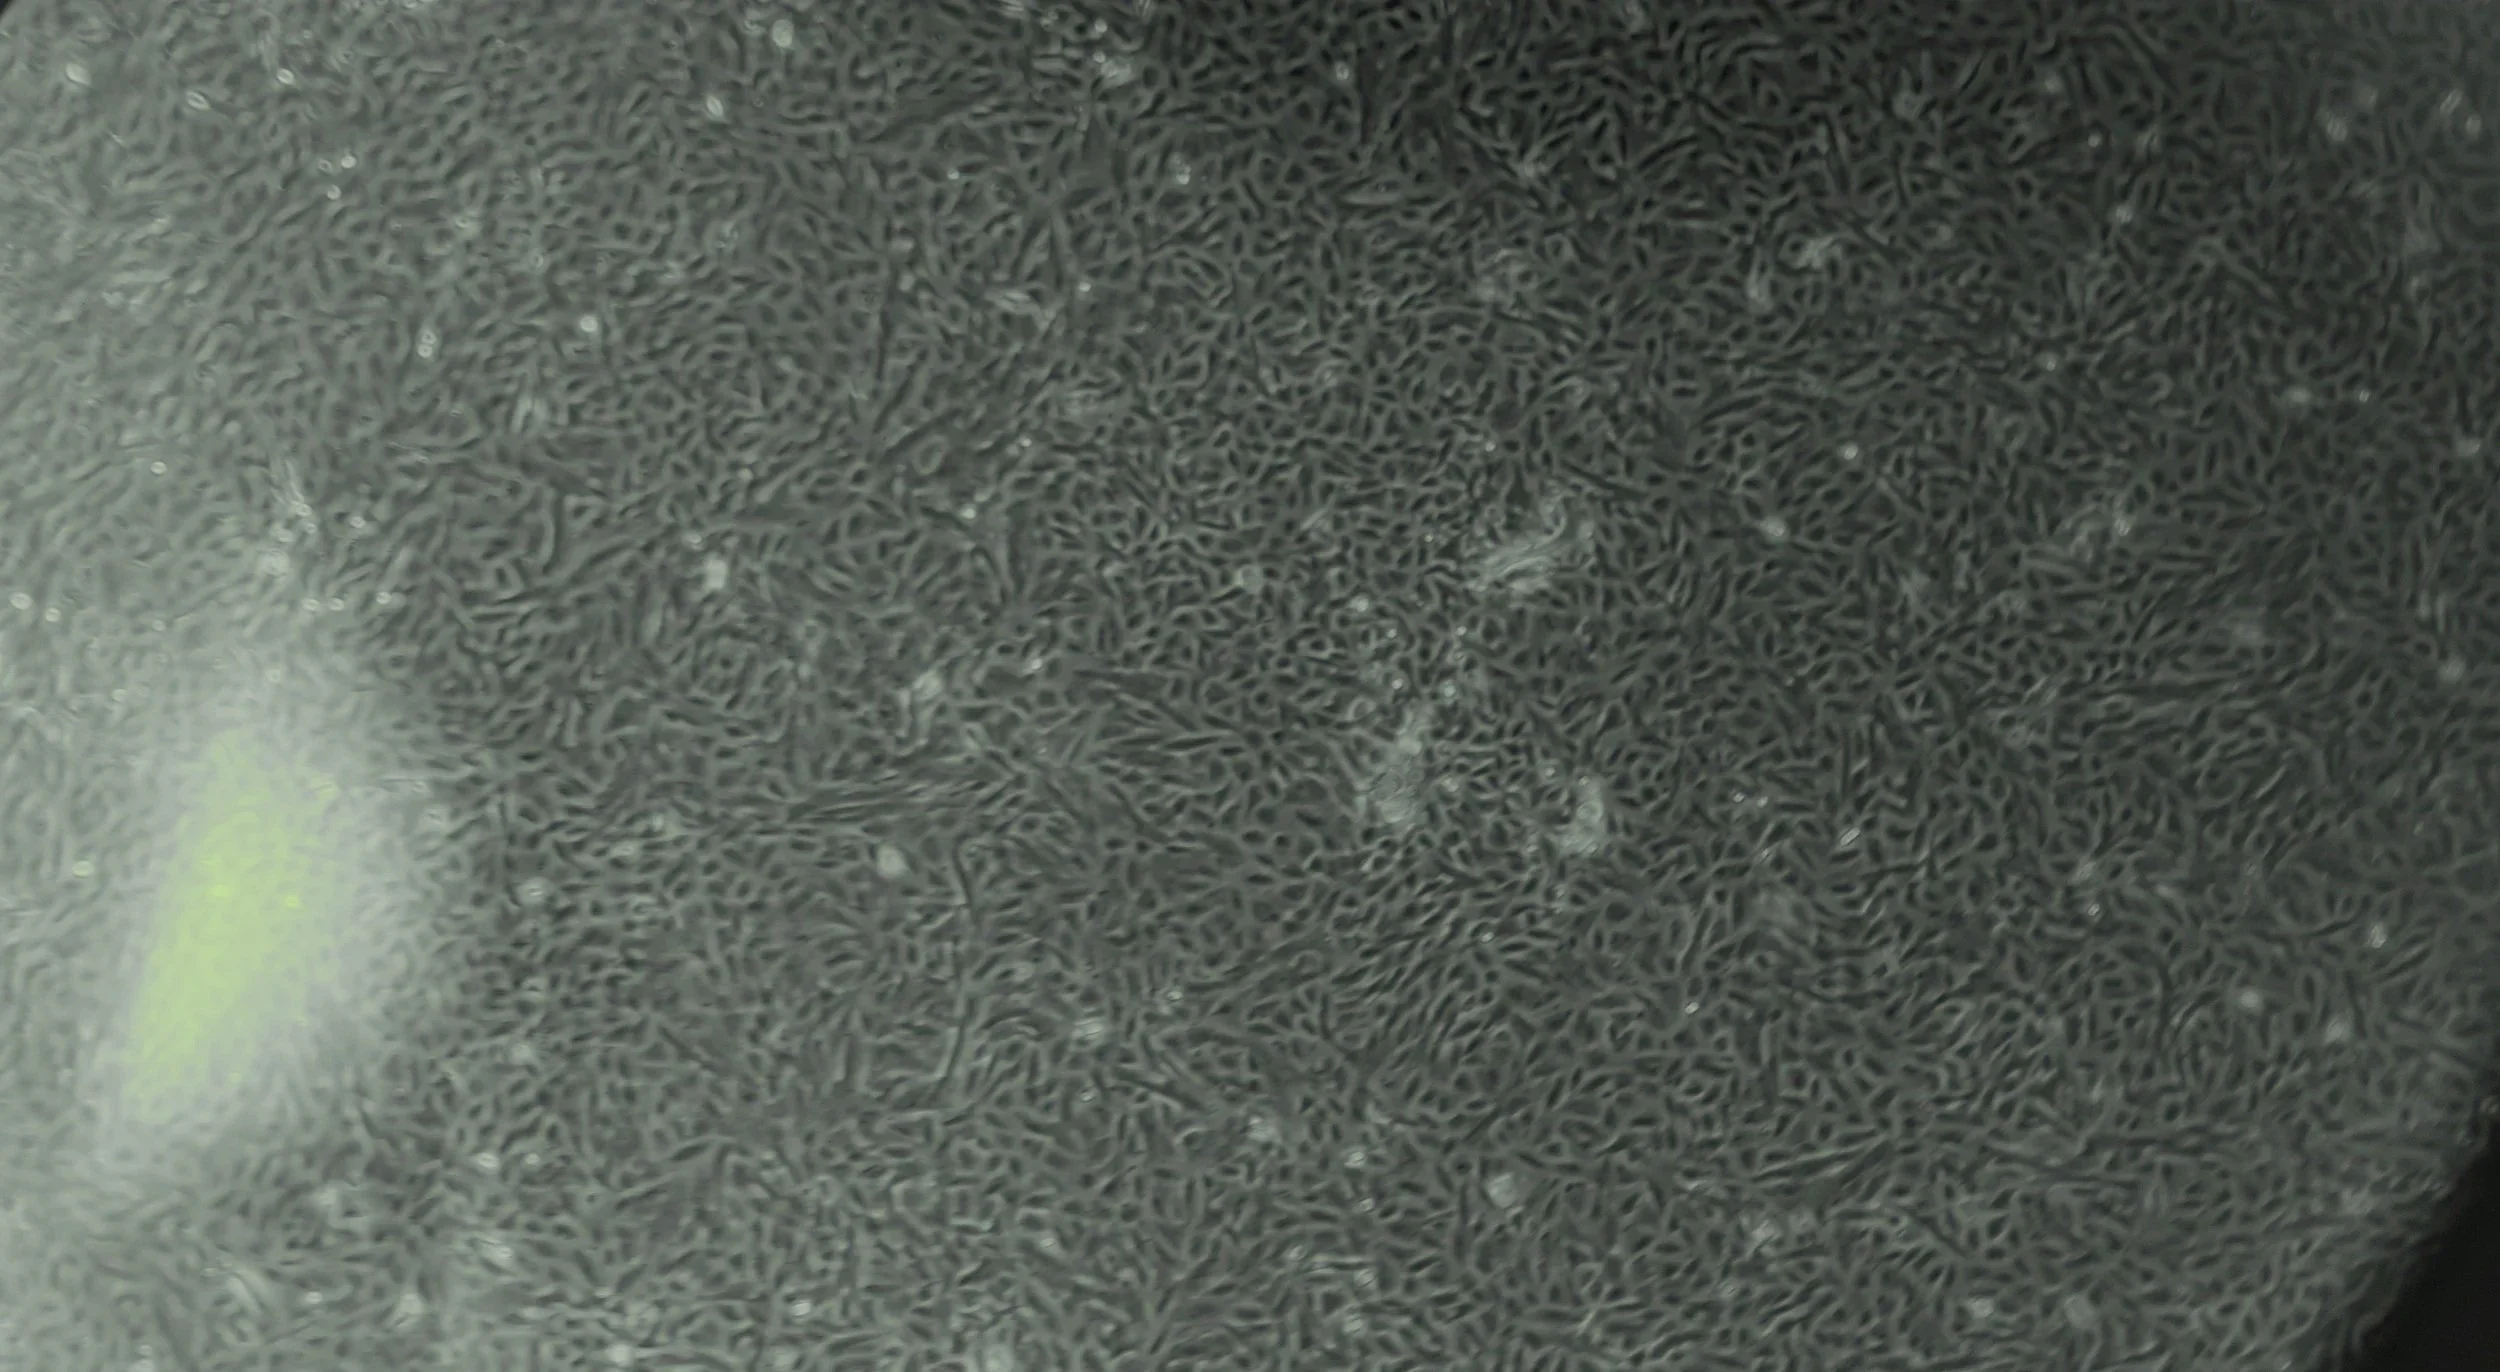

At The Renue Regenerative Medical Centre and Labs, we provide high-quality holistic regenerative treatments and therapies to help you have the quality of life you deserve.

Learn more about our medical services, and find how can we help you to achieve your health goals.